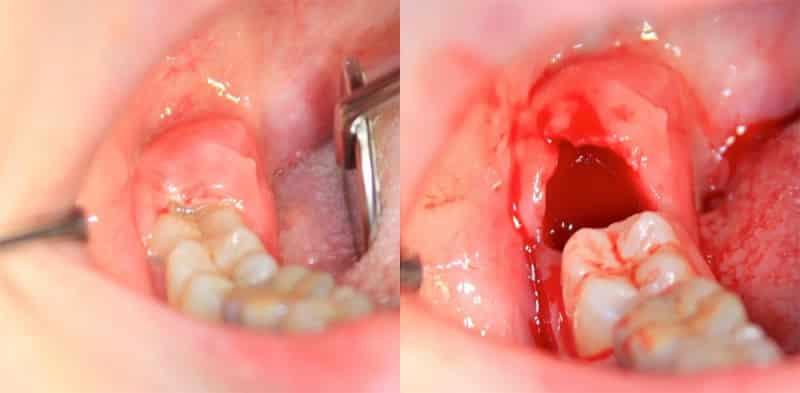

После удаления зуба, ваш врач обязательно даст вам рекомендации по процедурам, которые помогут десне зажить быстрее. Если удаление было сложным и потребовало разрезания десны, время восстановления лунки будет дольше. В таких случаях, вам могут посоветовать полоскать рот различными травяными отварами, чтобы снять воспаление и устранить болезнетворные бактерии.

После удаления зуба в ране образуется защитный сгусток из крови. Альвеолит, или воспаление лунки после удаления зуба, чаще всего встречается после удаления молярных зубов в нижней челюсти. Это связано с более сложной анатомией этой области, что делает хирургическое вмешательство более сложным. Кроме того, инфекция, попадая в рану, может быстро распространиться в мягкие ткани и вызвать гнойное воспаление, особенно после удаления зуба мудрости.

Скорость восстановления после удаления зуба зависит от нескольких факторов, включая физиологические особенности пациента, опыт врача, место удаления зуба и возможные осложнения операции. В некоторых случаях, когда зуб уже отсутствует или разрушается во время операции, стоматолог может прибегнуть к разрезанию десны, что может замедлить процесс заживления. После удаления зуба образуется кровяной сгусток, который играет роль барьера для защиты от инфекций. Этот сгусток необходимо оставить на месте, чтобы предотвратить воспалительные процессы. В течение нескольких дней сгусток меняет цвет и постепенно заживает, а открытая рана затягивается грануляционной тканью. Полное заживление мягких тканей обычно занимает около 2-3 недель, но процесс формирования новой костной ткани может продолжаться несколько месяцев. После удаления зуба может наблюдаться отёк десны, который обычно сходит через несколько дней.